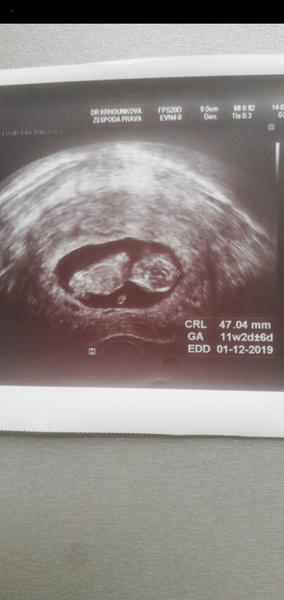

Ahoj holky, čekáme s přítelem první miminko.... Moc se na něj těšíme. Pohlaví nám pan doktor neurčí, musí počkat na další screening ve druhém trimestru. Ale prakticky všichni z rodiny vidí na fotkách z ultrazvuku kluka, co myslíte, může to být kluk??

Ahoj 🙋♀️ máte prosím nějaký tip? Fotka je z 12+2,dekuji 😊